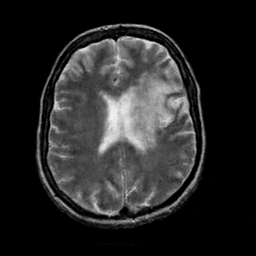

In this paper, we propose a bidirectional learning model, known as dual contrast cycleGAN (DC-cycleGAN), for medical image synthesis from unpaired data. Specifically, a dual contrast (DC) loss is formulated that leverages the advantage of samples from the source domain as negative samples to indirectly build constraints between real source and synthetic images via discriminators, and synthesize images more related to the target domain by enforcing the synthetic images to fall far away from the source domain. In addition, structural similarity index (SSIM) [35] and cross-entropy (CE) [48] are integrated into the DC-cycleGAN structure to avoid disappearing gradient information that is caused by a mean absolute error (MAE) and synthesizing irrelevant images. SSIM considers luminance [35] and CE converges fast as its back-propagation error is less than MSE [28]. As can be seen in Figs. 1 and 2, using SSIM and CE with dual contrast can generate more clear and accurate MR images as compared with that of MAE and MSE, and SSIM and CE without dual contrast loss. Although both SSIM and CE with dual contrast and without dual contrast generate similar CT images, SSIM and CE with dual contrast quantitatively generate better images as shown in Table 4. The experimental results indicate that DC-cycleGAN is able to consider more complex features such as structure in synthesizing images and produce remarkable results as compared with other state-of-the-art methods reported in the literature.

Tables 3 and 4 show the results of MR and CT synthesis, respectively. As can be seen, all components play vital role in both tables. SSIM & CE (w) performs significantly better than other losses in synthesizing MR images. This also can be seen visually in Fig. 1. In contrast, SSIM&CE (w) performs slightly better than SSIM&CE (wo) in synthesizing CT images, both generate more or less similar CT images (see Table 4).